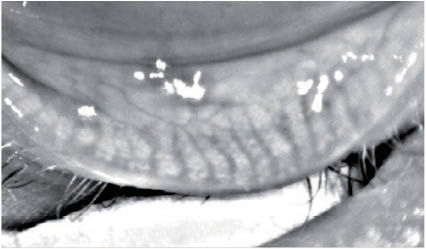

Meibo-scan

Ещё одним путём к лучшему пониманию состояния пациента является анализ мейбомиевых желез, также называемых мейбомиевыми канальцами. Прибор автоматически распознаёт границы века и корректирует контрастность для максимально четкой визуализации. Максимальная контрастность достигается при съёмке в инфракрасном диапазоне с дополнительным освещением от точечных источников.

Мейбография нижнего века